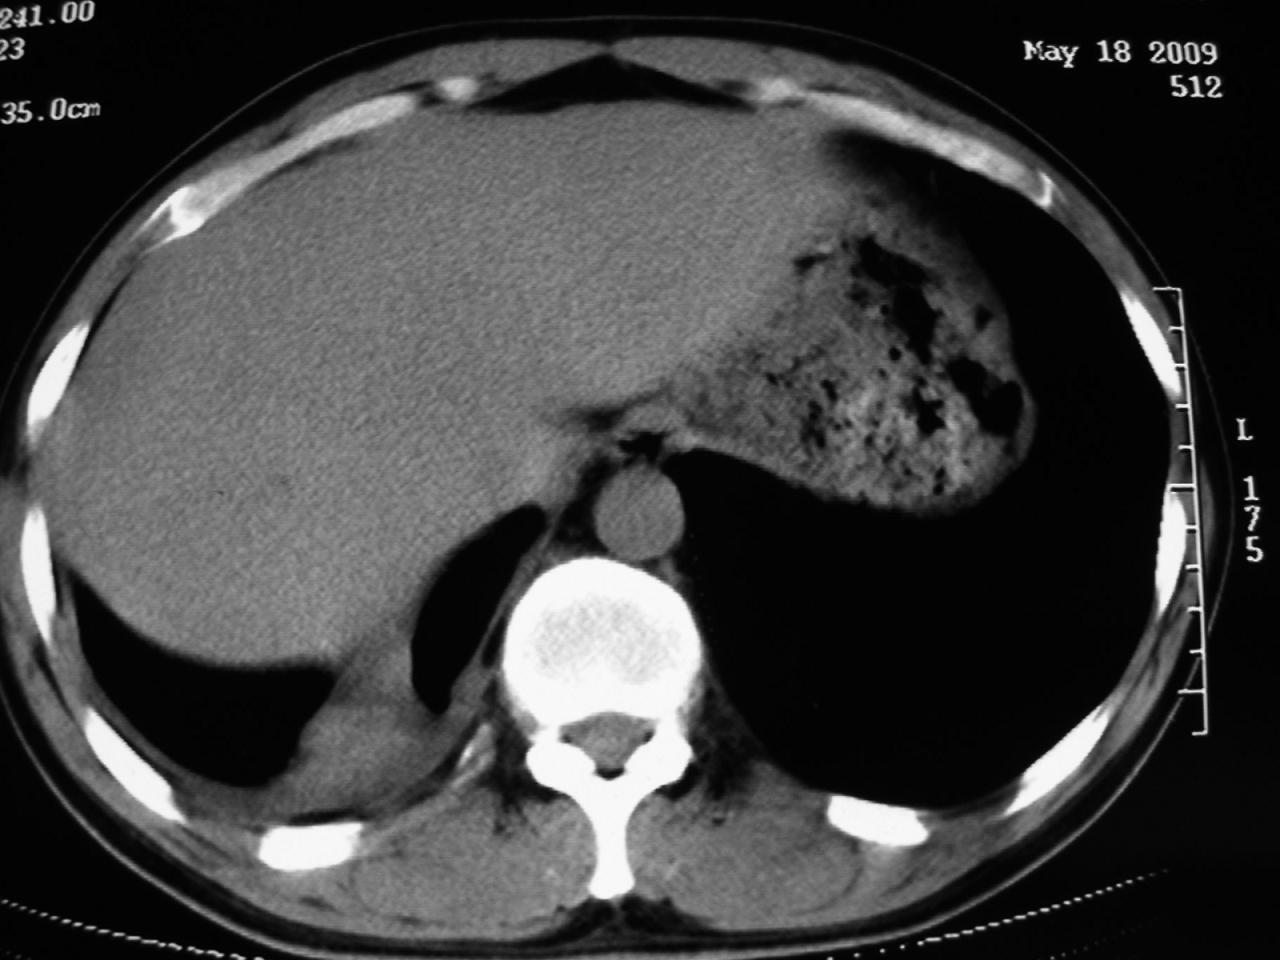

男,32岁,多年前右上肺结核,近期胸部不适,ct检查次序如上,上传主要层面,纵隔未见明显肿大淋巴结。

2009年5月18日:

本人初次(2008年12月20日ct片)诊断为右上肺结核伴右侧胸水!保守治疗后,遂复查ct胸水逐渐减少!最后(2009年05月18日)诊断为右上肺结核,右侧胸水吸收后伴包裹形成!从逐次ct检查上看,胸水吸收好转,只是从2009年05月18日ct片看到一个胸膜结节。临床医生及某肿瘤医院认为2009年05月18日ct片,右后胸壁结节,考虑为胸膜肿瘤!

本人还是倾向于右后胸壁的局限性包裹,胸膜结节密度不均匀,其内可见低密度区,考虑是由胸水吸收后胸膜增厚、粘连及周围肺组织包裹形成的征象;不倾向于胸膜肿瘤的诊断。